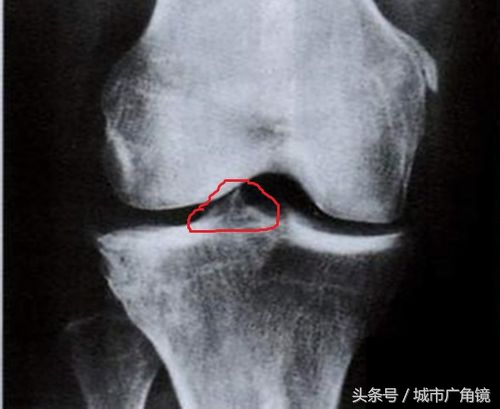

骨刺,其实应该叫骨赘,也就是我们常说的骨质增生,常见于中老年人群,多形成于骨骼的边缘,呈新生的骨组织,在X光片上呈现底部宽、尖端细的突起样表现。

随着年龄的增长,关节周围与软组织接触的地方因长期承受压力,造成软骨的磨损与破坏,从而刺激骨膜增生,逐渐在骨骼的边缘形成唇样的骨性突起,就形成了骨赘。

是的,不是“刺”,而更像是“唇”样的。